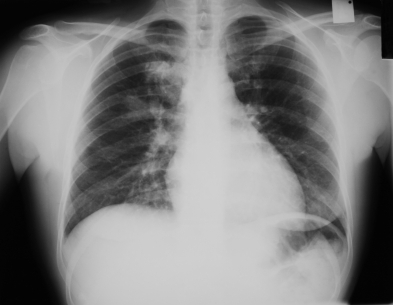

Диагностика микоплазменной пневмонии: Для точного установления диагноза микоплазменного воспаления легких проводят иммунологические и микробиологические исследования. Обязательно проведение рентгенологического исследования легких.

Диагноз атипичной вирусной пневмонии, как правило, ставится путем исключения других возможных причин пневмонии. Для этого назначают рентгенографию и анализ мокроты. Существуют методы, позволяющие выявить сам вирус в организме больного.

Медицинские процедуры, проводимые при заболевании атипичная пневмония: Рентген, Мазок из зева на Хламидии, Мазок из зева на Микоплазму, Мазок из зева на Легионеллез, Серология